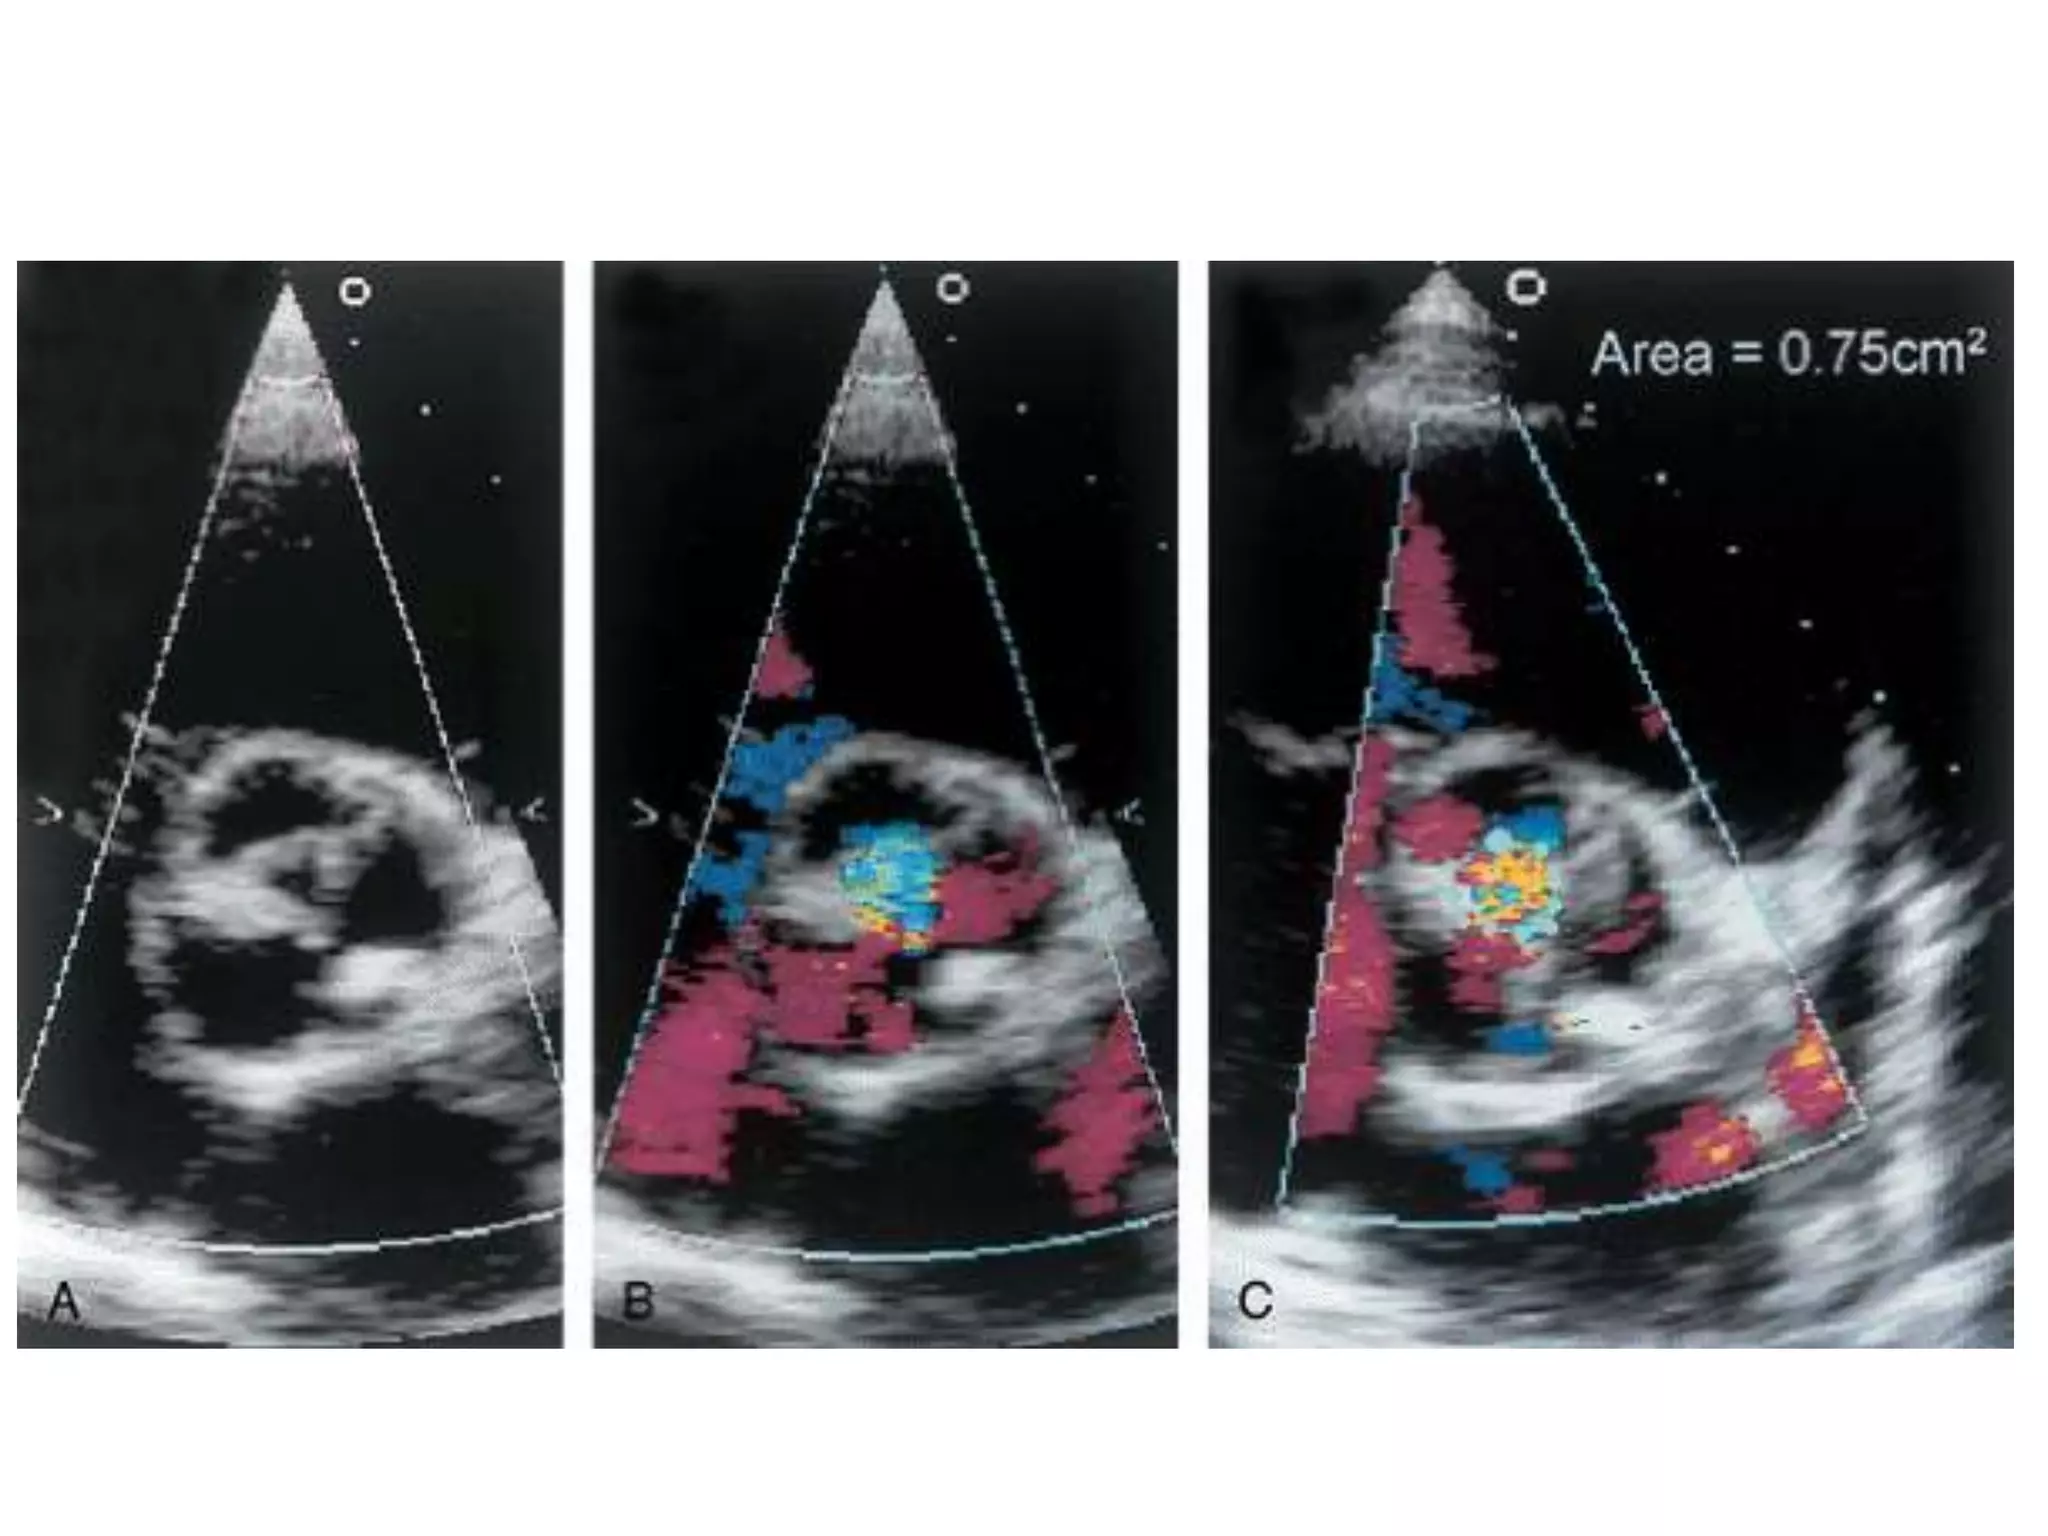

• Regurgitant jet area measured from PSAX view

at level of LVOT

• LVOA measured at end diastole at same site

• Ratio calculated